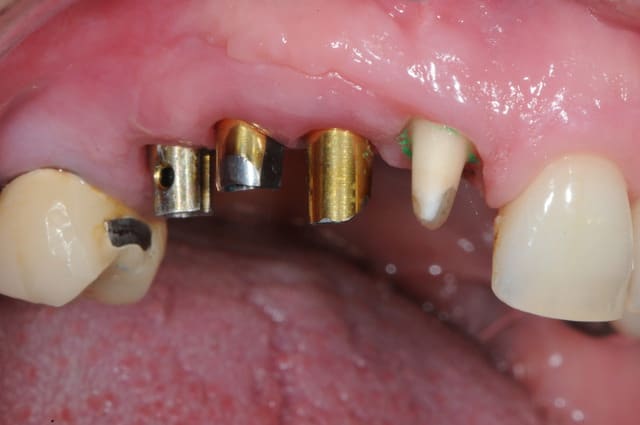

pose implants

piliers